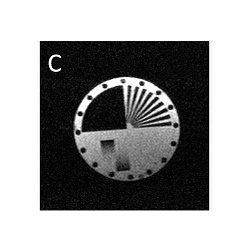

diagram of free radical phantom (diameter 2 cm)

0.02 tesla EPR-off image of phantom

0.02 tesla EPR-on image, showing Overhauser enhancement in regions containing free radical. PEDRI imagers normally use low-field magnets with magnetic fields of about 0.01 tesla (as opposed to the 1 tesla or so used in clinical MRI systems). This is because the ESR frequency is 659 times the NMR frequency in a given magnetic field. So, in a 1 tesla magnet, the ESR frequency would be 28 GHz, well into the microwave part of the electromagnetic spectrum, which would cook any biological sample being imaged! Reducing the magnetic field to 0.01 tesla brings the ESR frequency to a more manageable 280 MHz.